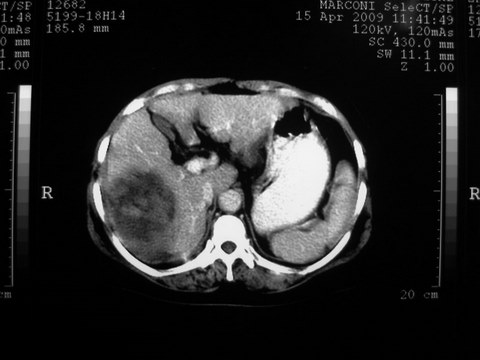

患者 女 51岁 两天前感觉上腹疼,无明显诱因,b超示肝右叶囊实性占位,边缘清楚,其内回声不均匀,ct增强如图,大家看看是什么 ,病人一年前及两月前b超检查只是提示胆囊炎

外院术后,证实肝癌合并出血

特点:1,病灶发展迅速,(2月前正常)[br] 2,囊实性,且并边界清晰光滑,呈右后叶赘生性。囊性区无强化,实性部分较多轻度强化,边界欠清。考虑囊腺癌或囊腺瘤。

出病理 中分化肝细胞癌合并出血